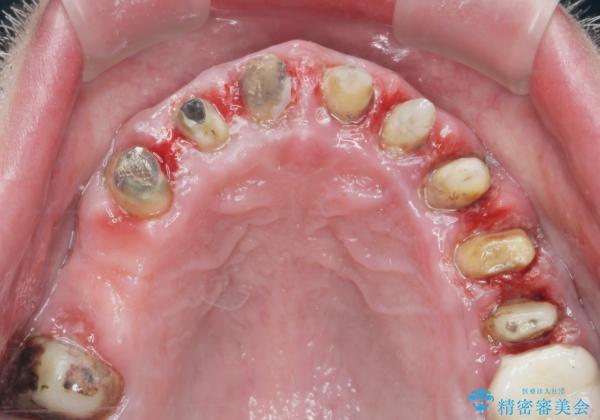

歯周組織検査を行うと歯ぐきからは容易に出血し、X線検査より歯とセラミッククラウンの適合が悪い(ピッタリと合っていない)状態が示唆され、歯ぐきの炎症を惹起している状態でした。

セラミッククラウンを除去し仮歯を装着し、歯周外科手術を行い歯ぐきの状態を改善したのち、適合の良いセラミッククラウンを再作製をする治療計画としました。